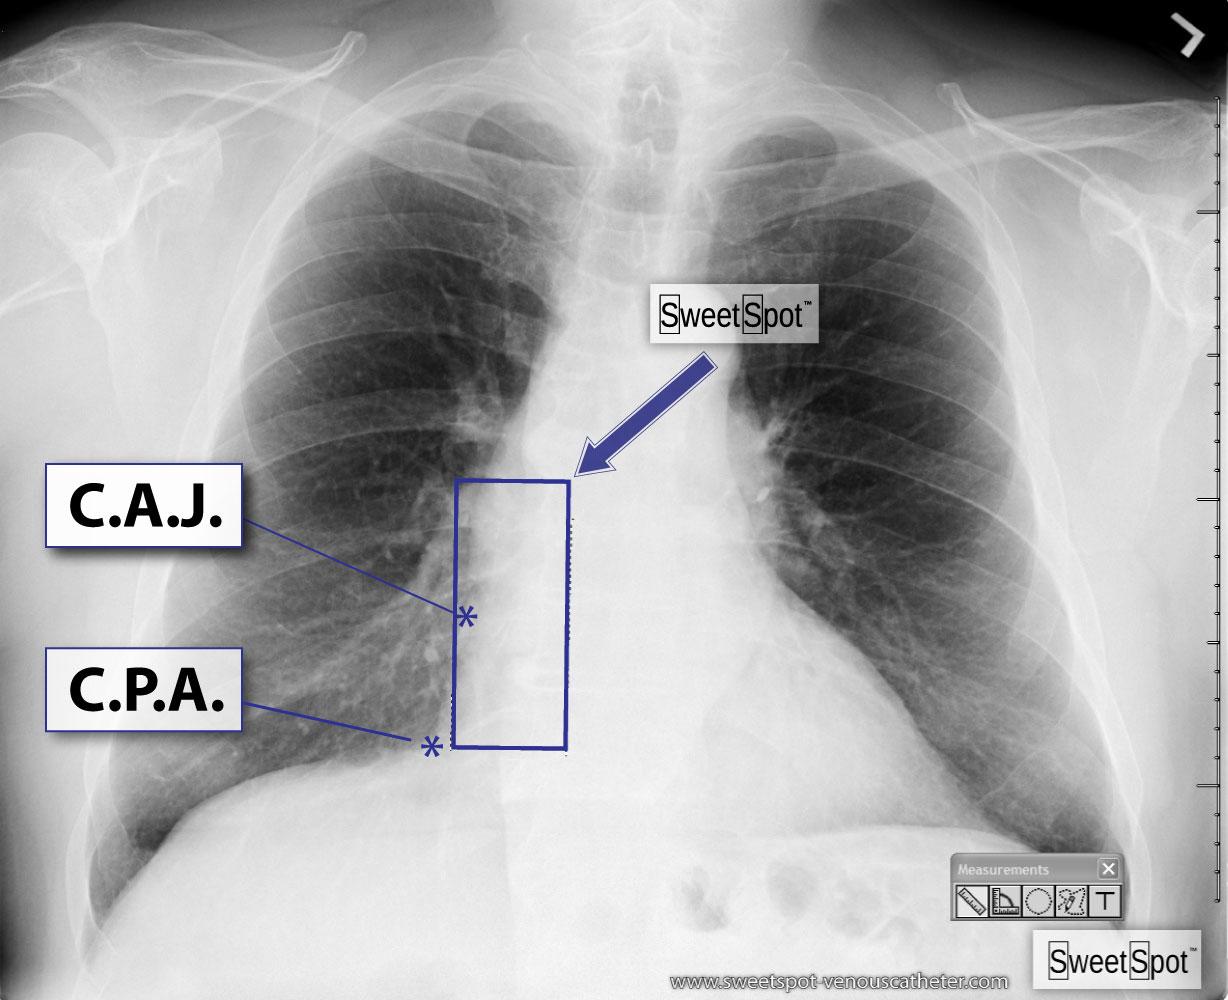

Figure - 01

CXR Sweet Spot™ Box Measurements |